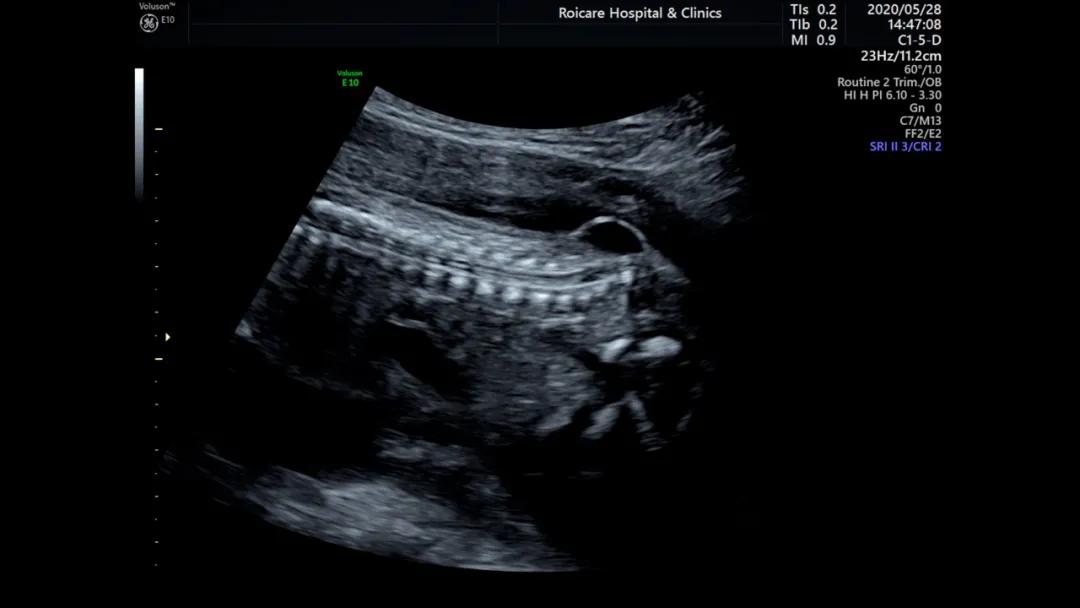

骶尾部脊柱裂伴脊髓脊膜膨出